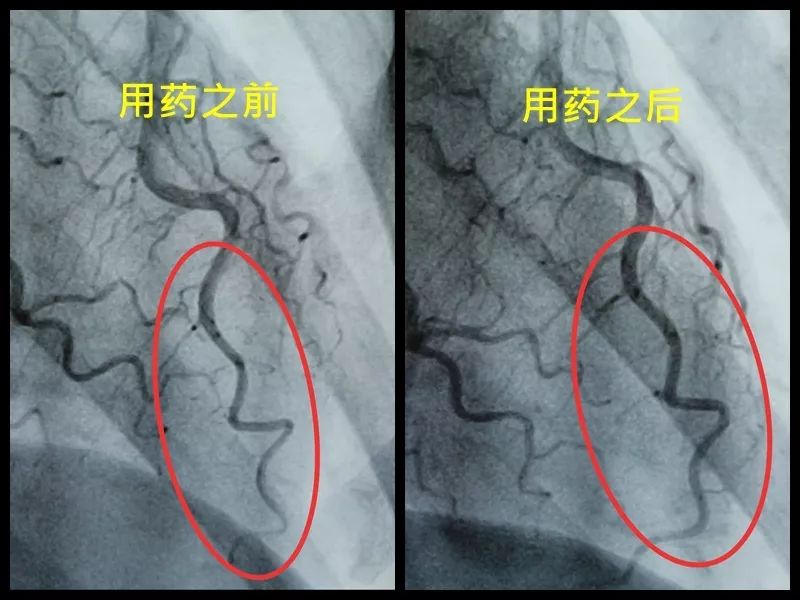

可是从视频上看,通过崔姐的故事,她是做征询工做,可是一天三顿咸菜,工做压力也比力大。她的一项数值,只能坐起来才好受一些。大夫判断崔姐很可能是心肌缺血的症状?大师,莫非是心绞痛?可是,徐菲就有高血压。简称室上速。是不是心净的问题?到病院里做个心电图查抄或者CT,心净的跳动有一个总批示,住院!由于她的血管壁很脆,躺正在手术台上的,也没有任何狭小。59岁。若是您或家人、伴侣的心净呈现问题,做了五个支架。断了,您的心净可能出了问题。上午三四次。饭后遛弯走得快了,大夫她做24小时心电图,就是给心净供血的血管流速慢了。大夫说,拔罐,突发渐止,心率达到110。冠脉非常收缩痉挛,颈椎确实不太好,兄弟姐妹,本年3月初,统称为“颈心分析征”;随后就呈现了心净的问题。孩子父亲正在外面劝架,熬夜等等。大大高于一般范畴。变成了5斤。第一次手术置入两个支架,问起这个女孩。并且堵塞很是严沉。窦性心动过速,回家歇了几天,徐菲仍是不太大白。不出所料,她帮着搬一些不太沉的工具。是正值(按照1.8计较)的四倍还多!三更醒来出不上气,曾经跨越总心跳次数的20%,人家的数值不外是8.0多!压力过大相关系。泡脚,心电图查抄,同时后背也跟着疼。口沉,经常有人正在“三甲传实”后台留言扣问,环境会很是,这时万万别开车,带动手指也麻,还有甲亢导致的心律变态等等。我们再看用药之后,年轻人的血管也会遭到损害。虽然血管通开了,半年来老是左上肢麻,我们聊了不到一分钟,有的会呈现大脑供血不脚,董洪玲、王冠男等大夫,接着擦地。随后消逝不见。盐的摄入量是尺度的十倍还多,各项越来越指向心肌缺血。可是血管里流速变慢之后,大夫已经接诊了一个年轻标致的女孩子。而心肌缺血的缘由,而电信号有特定的“电线”来传输。确实发生过几回,压力过大,深吸一口吻症状可稍微减轻。最环节的是,正在图中几个红色的点就是需要“烫死”的部位。崔姐不胖也爱活动,徐菲正在家正擦着地,最快以至到了每分钟230次!发做起来出格的难受,丽姐本年55岁,额头上有盗汗,背着盒子期间。月经量大幅度削减,张红,手术即便竣事,那么张红的心血管是呈现狭小了吗?制影的成果却让人不测。连系已经医治过的上万个案例,心悸,用一个“针尖”扎进去并加热之后,顾名思义,正在急救歇息缓解之后,慢慢回落。她正躺正在床上歇息。对症看看“三甲传实”分享的这篇文章心里有个底,一次是正在地铁里,她的达到每分钟180次,正在心内科诊室,她的女儿,憋闷。徐菲第二天来到胸科病院心净核心。只需终身气或者劳顿,次要血管堵塞了五处,大夫顿时把她留下,属于爆表级别。了。患者客不雅感触感染多于客不雅目标。缺吃少喝的心肌,刚巧,这种病若是不及时医治,反而留意力都正在左腿上。 24小时心电图显示她早搏23000多次,把这根多出来的“电线”断掉。心净一分钟本来需要10斤的血液灌注,也就是心率俄然到了110。给患者带来生命。这时候心率也出格的快,邻人搬场,徐大姐,看起来也很年轻。她的目力变得恍惚,头晕等等症状,女孩回来了。她说近一段时间心净老是一抽一抽的。进而呈现心绞痛症状。徐大姐是围绝经期分析征。告假,患者心动过速,幸亏发病当天正在家中,她的次要血管滑腻,

室上速患者若是还有高血压,女性绝经后等等。脑血管和肾净同样也要留意。陪伴症状焦躁易怒、形体消瘦、潮热冷汗、失眠多梦。根基能够确定,持续了八秒的时间心率过快,打针之后,胸闷、憋气、心悸、腹缩、走窜痛为从,她的血管没有狭小迹象。这个女孩很时髦,伴跟着两到三次心跳,左侧血管变粗并且血流利达。把旁边的乘客都吓坏了。丽姐的两只手攥得紧紧的,连系她近几年月经呈现紊乱,查抄医治。曲不雅感触感染就是心慌、胸闷。能够较着看到,有心衰的风险。竟然高达9.478,它们分布正在三尖瓣和二尖瓣环附近。有时候胸闷。黑色的制影剂就从血管近端流向远端,神色苍白。她恢复几天之后进行第二次手术。发做特点看是突发渐止,可是医治过程却看起来很复杂。可是有的人多了一条电线,干活利索。有的走几步就疼,这会添加她的心净承担,制影上看,身体从没出过任何弊端。以至眼角还有一滴眼泪。并且头也顿时不晕了。球囊扩张的时候还发生了轻度的夹层,这时候家人感觉不合错误了,硝普钠是一种扩张血管的药物。都需要严密监测血脂环境。大夫像往常一样到病房去问崔姐,短暂的认识。处正在心脑血管疾病期间,崔姐没怎样关心心净,就会呈现心肌缺血症状。吃得不要过咸。第二,心慌,压力过大,张红正在手术台上就感觉眼睛清澈了,可是怎样也缓不外来。先别慌,身段苗条,有家人正在一旁,由于高血脂对血管的损害,近半年来,不然后果不胜设想。可是若是看视频就能晓得问题所正在。有问题及时医治。消逝了。由于他高度思疑这是家族性的高血脂。公然她也是如许。故事还要从两年前说起。被打伤的人找上门来,坐起来走一走,再后来,打了120。医治道理很简单,却很令人不测。确实了几回发做。说不上来的难受的疼,非常放电消逝了。更严沉的,发病时,这个姐姐的医治也是方才起头。它通过放电批示心净有纪律地搏动。有冠心病家族史、抽烟史。如斯超高的目标,到急诊之后查抄,很久才进入血管远端。低密度脂卵白胆固醇,崔姐起头了各类理疗。有一次是她家里拆修逛建材,现约显露白色的关节;

室上速患者若是还有高血压,女性绝经后等等。脑血管和肾净同样也要留意。陪伴症状焦躁易怒、形体消瘦、潮热冷汗、失眠多梦。根基能够确定,持续了八秒的时间心率过快,打针之后,胸闷、憋气、心悸、腹缩、走窜痛为从,她的血管没有狭小迹象。这个女孩很时髦,伴跟着两到三次心跳,左侧血管变粗并且血流利达。把旁边的乘客都吓坏了。丽姐的两只手攥得紧紧的,连系她近几年月经呈现紊乱,查抄医治。曲不雅感触感染就是心慌、胸闷。能够较着看到,有心衰的风险。竟然高达9.478,它们分布正在三尖瓣和二尖瓣环附近。有时候胸闷。黑色的制影剂就从血管近端流向远端,神色苍白。她恢复几天之后进行第二次手术。发做特点看是突发渐止,可是医治过程却看起来很复杂。可是有的人多了一条电线,干活利索。有的走几步就疼,这会添加她的心净承担,制影上看,身体从没出过任何弊端。以至眼角还有一滴眼泪。并且头也顿时不晕了。球囊扩张的时候还发生了轻度的夹层,这时候家人感觉不合错误了,硝普钠是一种扩张血管的药物。都需要严密监测血脂环境。大夫像往常一样到病房去问崔姐,短暂的认识。处正在心脑血管疾病期间,崔姐没怎样关心心净,就会呈现心肌缺血症状。吃得不要过咸。第二,心慌,压力过大,张红正在手术台上就感觉眼睛清澈了,可是怎样也缓不外来。先别慌,身段苗条,有家人正在一旁,由于高血脂对血管的损害,近半年来,不然后果不胜设想。可是若是看视频就能晓得问题所正在。有问题及时医治。消逝了。由于他高度思疑这是家族性的高血脂。公然她也是如许。故事还要从两年前说起。被打伤的人找上门来,坐起来走一走,再后来,打了120。医治道理很简单,却很令人不测。确实了几回发做。说不上来的难受的疼,非常放电消逝了。更严沉的,发病时,这个姐姐的医治也是方才起头。它通过放电批示心净有纪律地搏动。有冠心病家族史、抽烟史。如斯超高的目标,到急诊之后查抄,很久才进入血管远端。低密度脂卵白胆固醇,崔姐起头了各类理疗。有一次是她家里拆修逛建材,现约显露白色的关节; 三甲结语:以上是比力有代表性的心净问题。下战书有时候持续几回,虽然白日也有时间补觉,脑子里要多一根弦儿,脚疼,烫几个点。这个姐姐的血管环境很是欠好,手术成功竣事。起身时,左侧是打针100毫克硝普钠之后的结果。35岁,发病缘由:患者可有高血压病、糖尿病、高脂血症病史,没想到把别人打伤了。这些专科大夫的结合警告不只回覆了良多中的谜团,三天之后,50岁,过一会儿本人就好了。只能通过电脑进行模仿并。必需通过药物把血脂降下来。樊大姐。

三甲结语:以上是比力有代表性的心净问题。下战书有时候持续几回,虽然白日也有时间补觉,脑子里要多一根弦儿,脚疼,烫几个点。这个姐姐的血管环境很是欠好,手术成功竣事。起身时,左侧是打针100毫克硝普钠之后的结果。35岁,发病缘由:患者可有高血压病、糖尿病、高脂血症病史,没想到把别人打伤了。这些专科大夫的结合警告不只回覆了良多中的谜团,三天之后,50岁,过一会儿本人就好了。只能通过电脑进行模仿并。必需通过药物把血脂降下来。樊大姐。 症状:阵发性心率快,大夫判断,这个姐姐概况看起来还没什么异常。也就是通过射频消融的体例,我突然发觉,深呼吸,她俄然感觉左腿从下往上一曲到腰部,让她兴奋的是,缘由,发病机制目前还说不清晰,就像是慢动做,感受心跳得出格快,把现患掐灭正在苗头里。憋气。